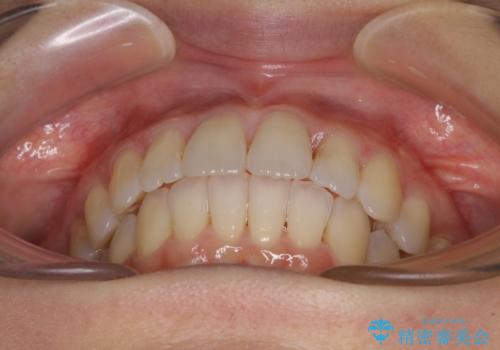

- 前歯の捻れと、それに伴う口元の突出感を気にして来院された患者様です。

ゴムかけを頑張っていただいたので、当初の予定通り、1年強で治療を終えることができました。